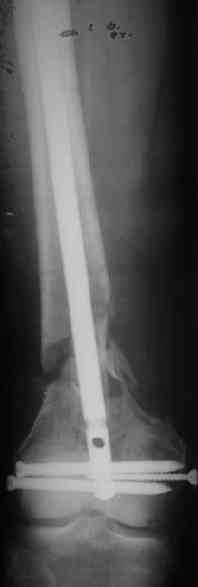

Удалили ластину без проблем. Выявилась значительная подвижность. В этих условиях сразу пропала мотивация к постепенной коррекции аппаратом. Попробовал восстановить длину, введя между отломками spreader. Отчасти удалось. Тогда защили рану, наложили спицевой дистрактор (2 спицы в дистальный отдел и 1 вверху). после этого был убран и спонгиозный винт. И сделали антгерадное штифтование, как говорится, "по принятой в

клинике методике".

Длину восстановили, возможно, даже с изьбытком, ну да динамизируем пораньше. Введенные в овальное отверстие дистальые винты имеют угловую стабильность. Снимки приложены. Заранее спасибо за критику и комментарии.

Довольно симпатично получилось. Не сомневался, что будет именно такой антеградный реостеосинтез.

Была ли педресация на столе после окончательной фиксации? Уверен ли ты, что "угловая стабильность" дистальных винтов позволит агрессивно заниматься разработкой движений в коленном суставе?

Nicely executed surgery with good planning resulting in great looking x-rays but not the best the way to deal with this fracture. Earlier fracture was having slight translation with no angulation and no instability, now ur fracture is distracted with potential instability as your construct is not the best suited to this place, so more likelihood of non union or complications.

Should have preferred a locking plate if at all u wanted to reoperate and

added copious bone graft.